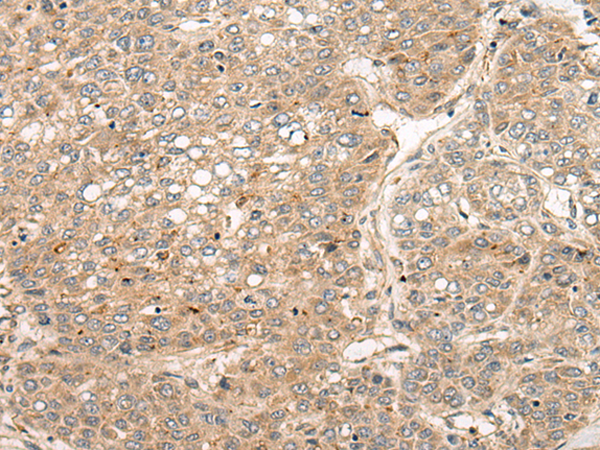

IHC positive control: |

Human liver cancer |

IHC Recommend dilution: |

40-200 |